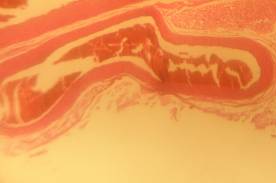

Histopathology

All rats were sacrificed, and their aortas were isolated for histological preparation. The aorta samples were fixed in 10% formaldehyde solution, and their slides were prepared. The slide preparations (6-8 µm thickness) were stained with hematoxylin/eosin. Each slide was scored based on the aorta conditions. The scores ranged from 0–4 with the following criteria: 0 normal condition; 1 if elastic fibres thickening was found; 2 if elastic fibres fragmentation, some foam cells, and fibrosis were found; 3 if smooth muscle proliferation was found, and 4 if plaque ulceration or plaque lipid calcification was found [10].

Morphological structure of aorta’s rats

Aorta’ slide was made every week for one month. Each group of the rats was killed, and the aorta’s rat was observed. From the morphological structure of aorta’s rat, atherosclerosis was scored as follows: on 4 point: 0, normal; 1, widening of elastic fibers with few foam cells; 2, fragmentation of elastic lamellae with numerous foam cells and fibrosis; 3, smooth muscle cells proliferation, medial lipid infiltration and fibrosis; 4, lipid-calcic plaque or ulcerated plaque [10].

The rats (n=4) from each group were sacrificed every week to observe the morphological structure of the aortas. From the lesions, it showed that AND could help chance severity aortic atherosclerosis. The score varied from group A1 until group A4. The aorta morphology of group A1 showed that one aorta had a widening of elastic fibers with few foam cells (score 1) and three aortas had the proliferation of smooth muscle cells (score 3) (fig. 5 A1). AND administration for four weeks could repair aorta condition. Group A4’ aorta morphology showed that three aortas became normal (score 0) and one aorta still had a widening of the first interlamellar (score 1) (fig. 5 A4). Atorvastatin administration could also help changing the severity of aortic atherosclerosis. The score also varied from group B1 until group B4. The aorta morphology of group B1 showed that one aorta had a widening of elastic fibers with few foam cells (score 1), two aortas had fragmentation of elastic lamellae with numerous foam cells and fibrosis (score 2), and one aorta had the proliferation of smooth muscle cells (score 3) (fig. 5 B1). Atorvastatin administration for four weeks could improve aorta condition. Group B4’ aorta morphology showed that two aortas became normal (score 0) and two aortas still had a widening of the first interlamellar (score 1) (fig. 5 B4). Contrarily, the morphological structure of atherogenic rats was getting worse week by week.

Fig. 5: Morphological structure of aorta in albino Wistar male rats 40x. A1, A2, A3, A4 is morphological structure of aorta’s AND rats fed atherogenic diet for 2 mo and continuing with AND for 1 w, 2 w, 3 w and 4 w; B1, B2, B3, B4 is morphological structure of aorta’s atorvastatin rats fed atherogenic diet for 2 mo and continuing with atorvastatin for 1 w, 2 w, 3 w and 4 w; C1, C2, C3, C4 is morphological structure of aorta’s rats fed atherogenic diet for 9th week, 10th week, 11th week, 12th week; D1, D2, D3, D4 is morphological structure of aorta’s rats fed regular diet for 9th week, 10th week, 11th week, 12th week. Black circle (O) = score 1; green circle (O) = score 2; red circle (O) = score 3; blue circle (O) = score 4